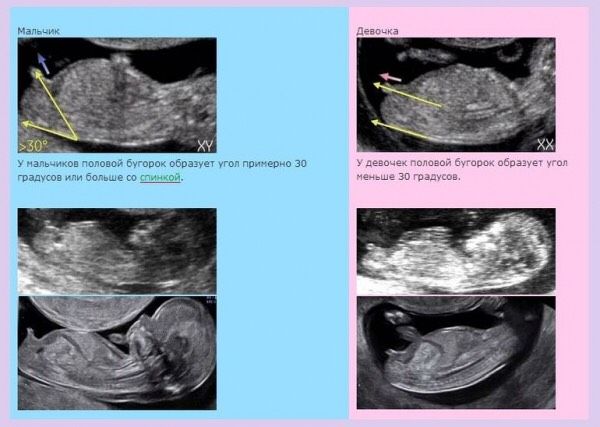

Дело в том, что у меня по всем ощущениям мальчик, а на скрининге сказали, что больше похоже на девочку, так как половые органы маленькие и положение пипки почти параллельно спинке, что судя по картинке, говорит о девочке.